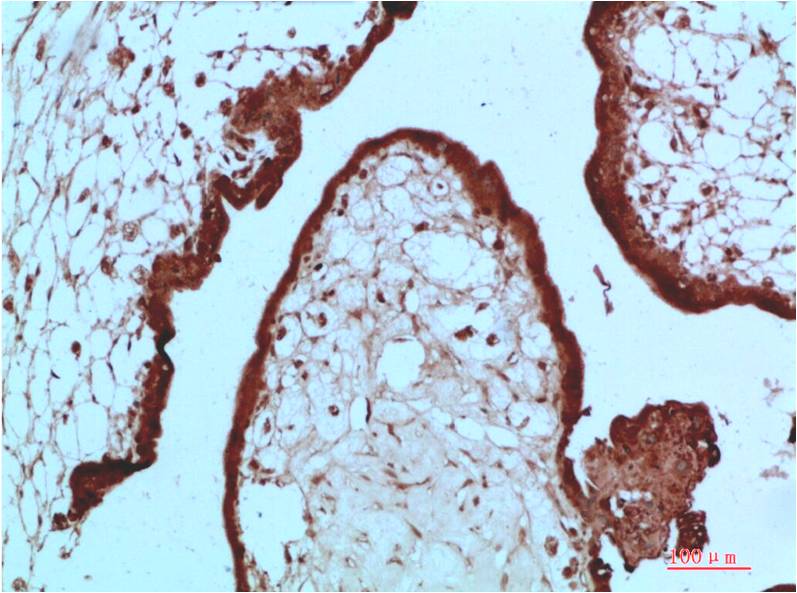

Immunohistochemistry analysis of paraffin-embedded Human Placenta Tissue using HP1 alpha antibody High-pressure and temperature Sodium Citrate pH 6.0 was used for antigen retrieval. |